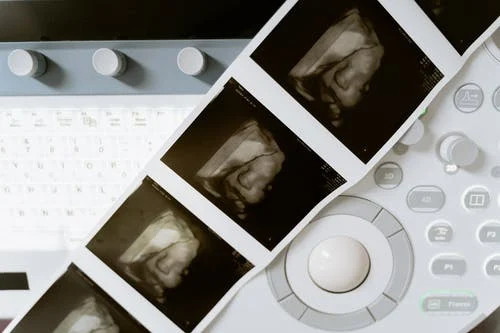

Menurut yang Mama baca dari Pregnancy Birth Baby, kebanyakan pemeriksaan USG ini dilakukan setelah 10 minggu kehamilan. USG ini merupakan proses pemindaian ultrasound yang menggunakan gelombang suara untuk melihat bagaimana keadaan janin yang ada di dalam perut.

Nantinya, hasil informasi seputar USG akan dicetak dalam sebuah foto print out. Kalau dilihat-lihat dalam hasil USG tersebut terdapat beberapa keterangan. Sebenarnya kita bisa saja sih menanyakan hal tersebut pada dokter kandungan. Tapi enggak ada salahnya juga kok untuk Mama-Mama lebih detail mengetahui istilah yang terdapat pada hasil USG ini.

Mengetahui hasil USG ini penting bagi Mama-Mama agar lebih memahami bagaimana kondisi janin yang ada di dalam kandungan. Termasuk arti BPD dalam USG. Bagaimana penjelasan selengkapnya? Cek di sini ya yang telah Mama rangkum dari berbagai sumber ini!